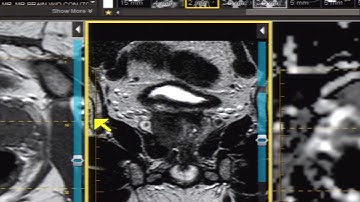

Introduction to Prostate MRI and PI-RADS: Approach and Principles